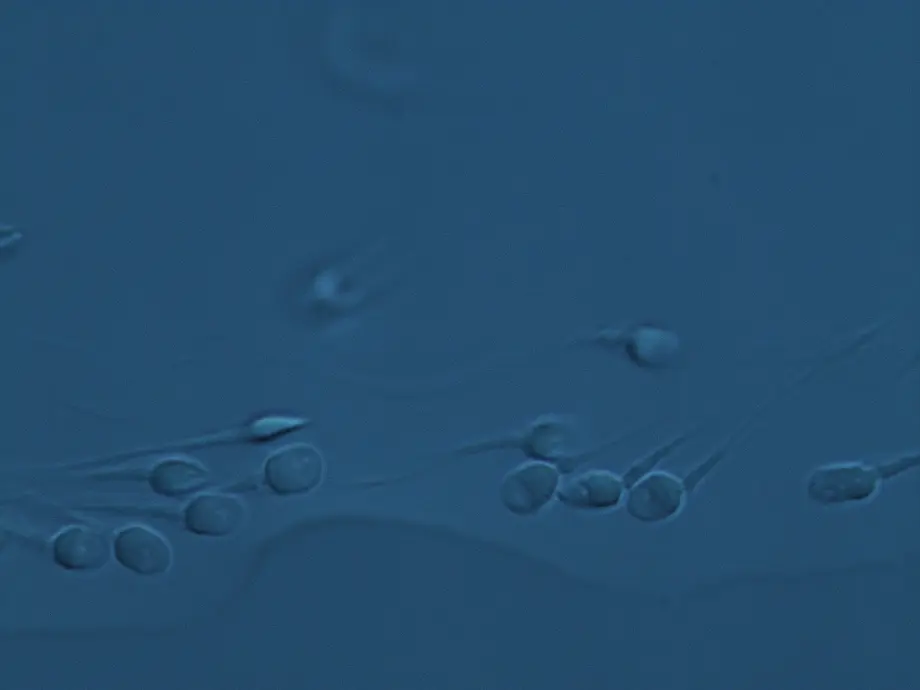

FertileChip es una técnica que permite seleccionar los espermatozoides con menor fragmentación del ADN mediante un dispositivo que simula las condiciones naturales del tracto reproductor femenino. De esta forma, se obtienen espermatozoides con mejor calidad genética para su uso en técnicas de reproducción asistida como la ICSI.

Gracias a su diseño microfluídico, FertileChip selecciona de manera eficiente los espermatozoides con mejor integridad del ADN, sin necesidad de realizar un procesamiento previo de la muestra, como el lavado o la capacitación. Esto no solo simplifica el procedimiento y lo hace más rápido y fácil de usar, sino que además reduce el riesgo de contaminación y mantiene las condiciones del espermatozoide lo más naturales posible.